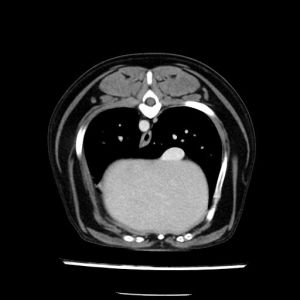

La lesione focale epatica , la ceus,la Tac e il chirurgo .